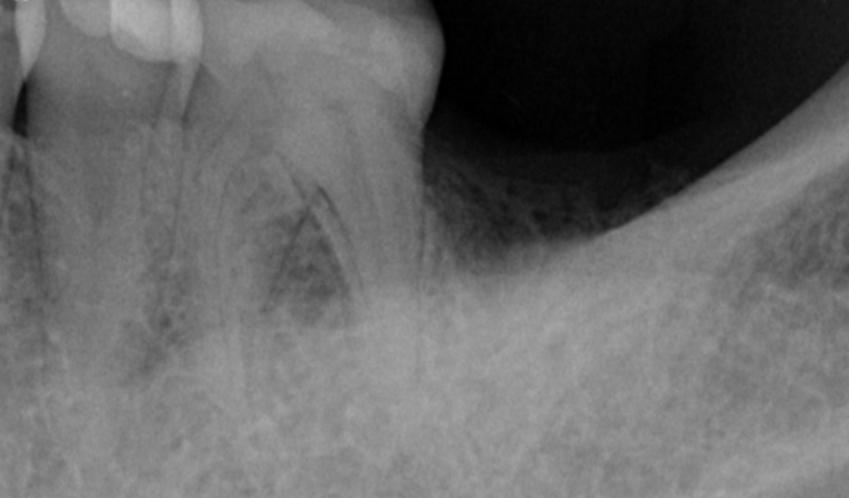

2. A follow-up examination was conducted three months after tooth extraction upon complete wound healing, and implant restoration was initiated.

Post-extraction wound healing status

3. During the implant placement, a certain degree of bone and soft tissue deficiency was identified in the edentulous area. Consequently, bone graft (0.25g) and a collagen membrane were simultaneously placed.

Bone and soft tissue deficiency in the edentulous area